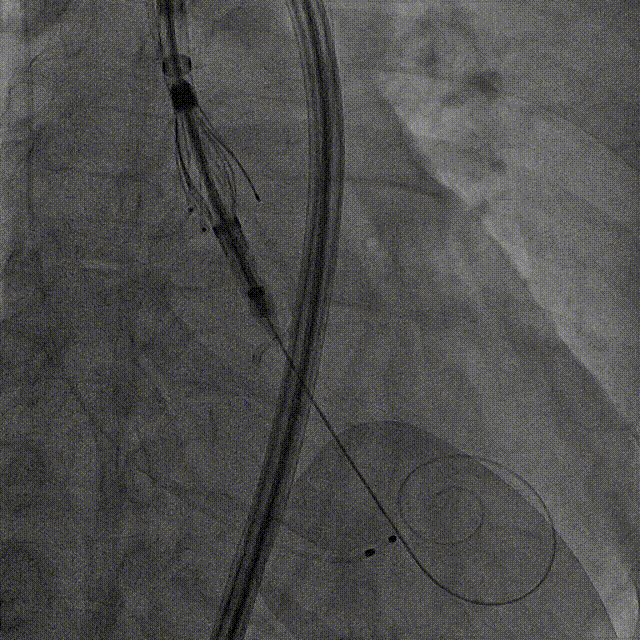

左冠造影

小右冠,弥漫性病变

LAD术后造影

根部造影

长鞘植入

输送器定位

右窦中心对齐

定位键窦对齐

无窦确认

右窦观察

左窦确认

深度确认

一键脱钩

术后造影